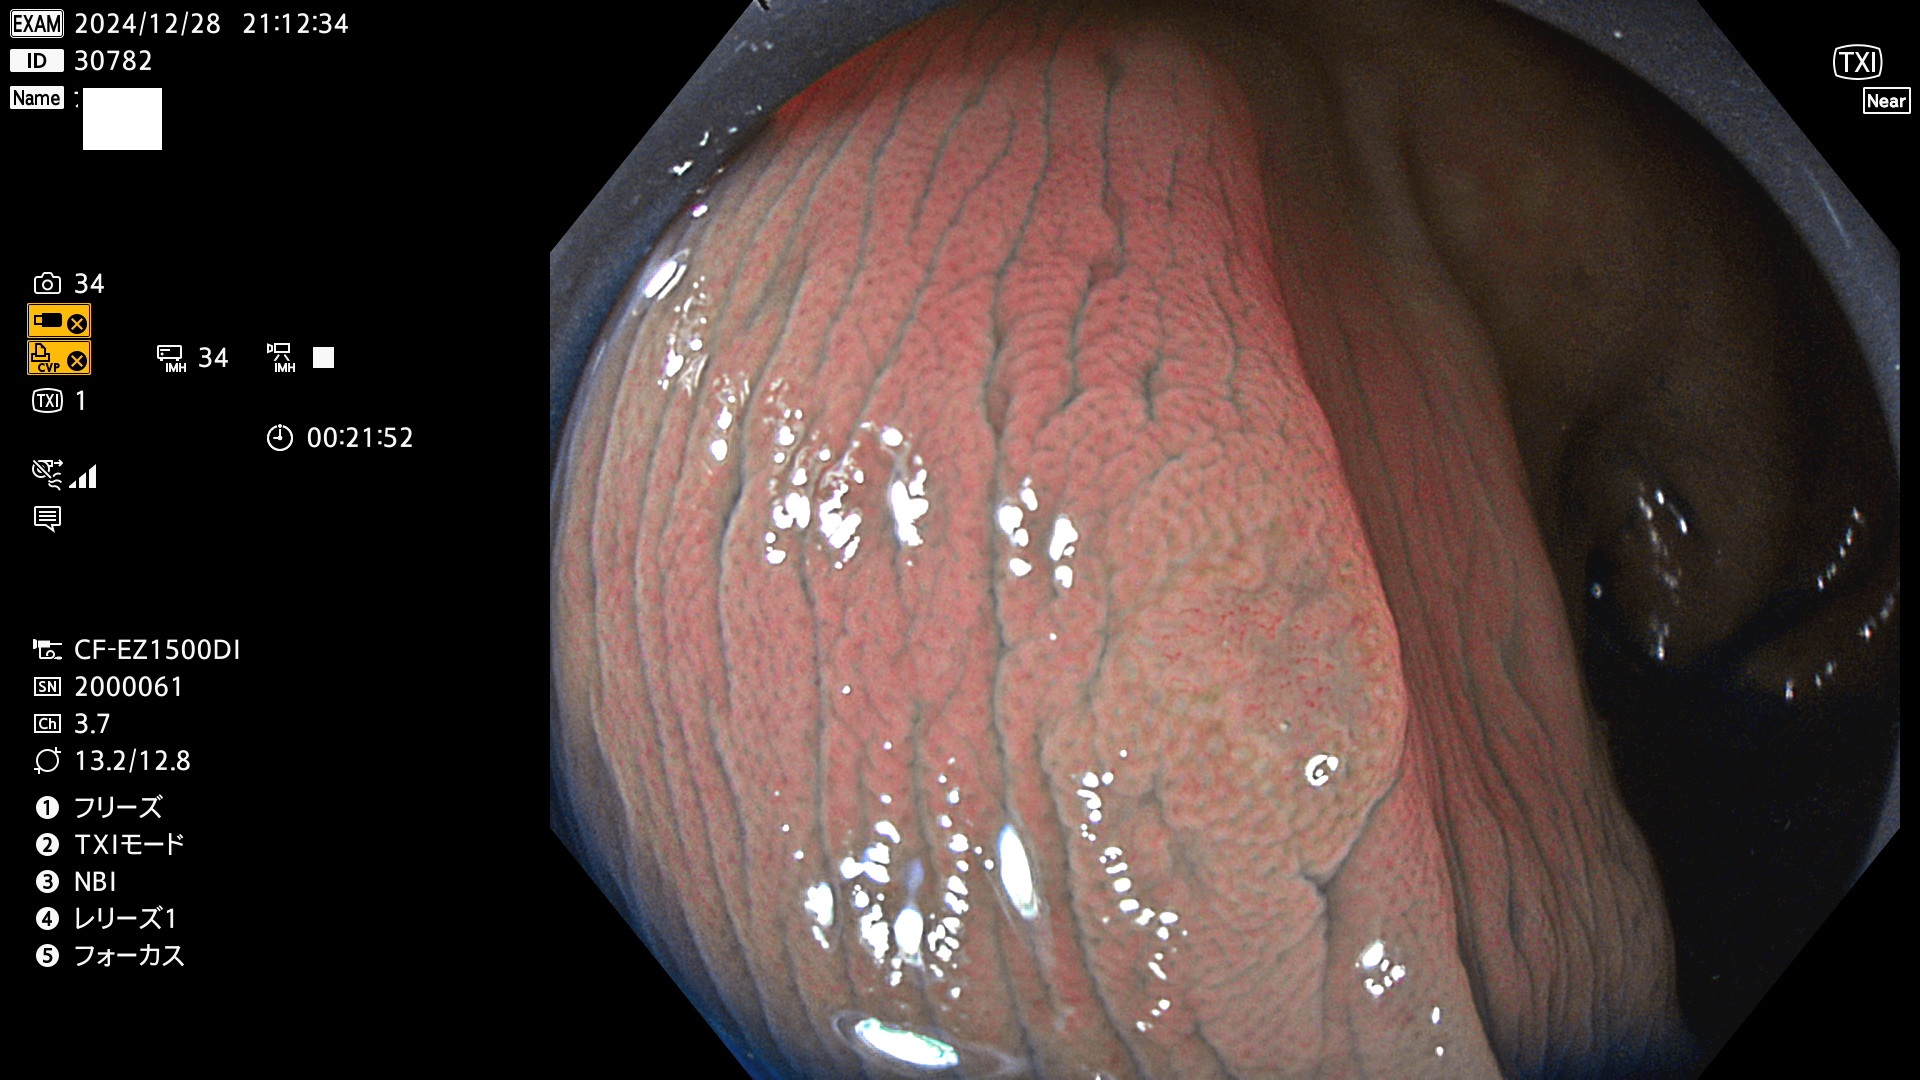

完全に平坦な物をUb、陥凹している物をUcと呼びます。最も発見が難しく危険な病変です。

毎週の検査(木・金・土・日)に発見されたUb、Uc型・腺腫を、その週の日曜の夜にUPし1週間、提示します。

抽出の対象期間 2024年12月26日〜12月29日の4日間(48件の検査)3件 (3/48=6%)